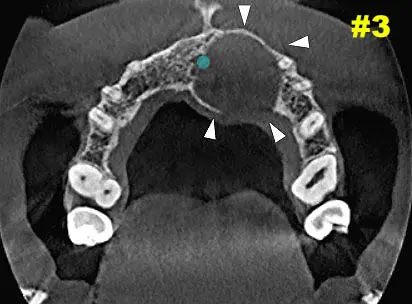

​Dicha lesión vemos que provoca expansión y abombamiento hacia piso de fosa nasal izquierda como también hacia cara palatina. Ver Imagen 2 Y 3. También se puede ver en una navegación  en cortes cada 1mm como se comporta la lesión - ver imágenes 4 y 5 (cortes transaxiales)